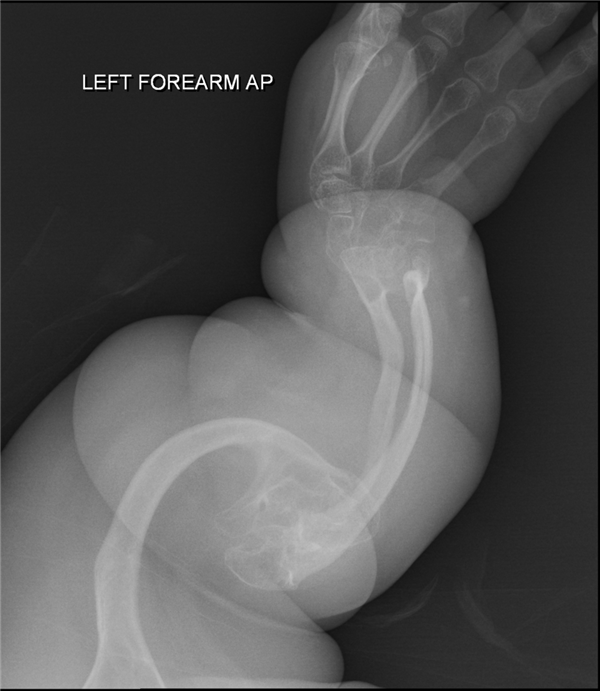

其他患者X光片——严重骨折

当时, 医生就给孩子拍摄了髋关节部位的X光片,结果在影像资料里发现了2处骨折,且处于不同的愈合阶段,说明2次骨折不是同一时间发生的。

接着医生又给孩子做了全身检查,在其他身体部位,又又又发现2处骨折,然后事态就升级了。

典型特征就是骨头脆弱,微小的外力就能导致骨折,比如打个喷嚏、翻个身、伸手够东西,成年后骨折情况会相对少一些。